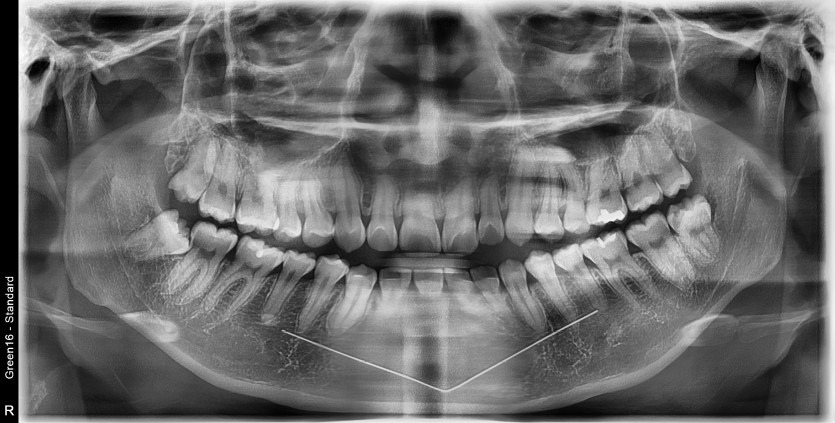

#18,28,38,48 사랑니 발치

구강 외과 전문의가 당일 발치했습니다.